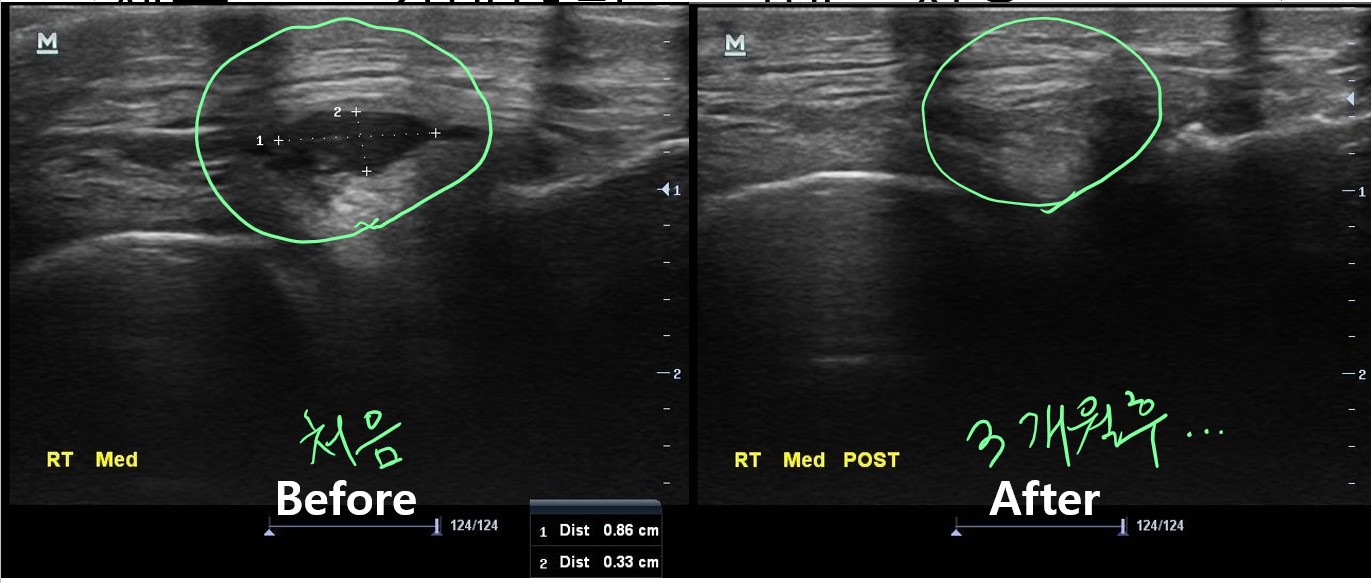

나 : 초음파 보면서 주사기로 물혹속 내용물을 제거해봐야 할거 같습니다.

나 : 이게 워낙 재발을 잘한다는게 문제입니다. 그건 우선 지켜봐야 할듯 하네요.

치료 후 3개월이 지난 현재, 이 환자분은 다행히 물혹이 재발되지 않아 큰 불편함없이 잘 지내고 있습니다. 아직 더 지켜보긴 해야 하지만요...

이런 환자를 만나면 초음파 검사의 필요성과 중요성을 다시 한번 깨닫게 됩니다.